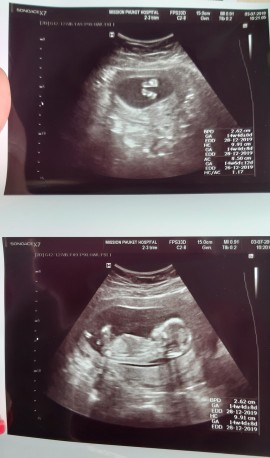

12ธ.ค.62 อาหมวย จร้